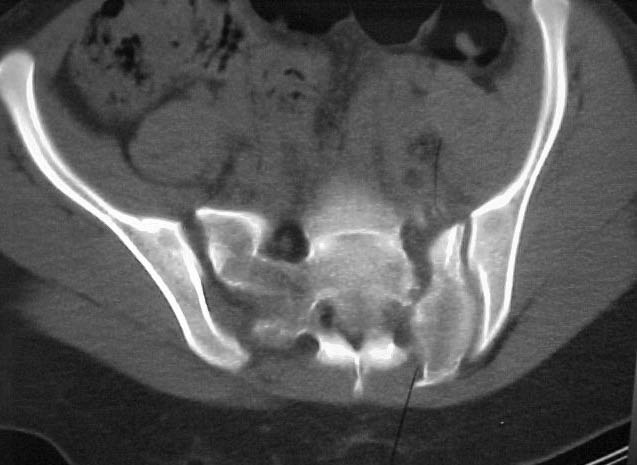

A 17 year old female involved in a car crash. Has a Type III lateral compression injury to her pelvic ring using the Young-Burgess classification. A windswept pelvis if you will. The images are included. There appears to be posterior displacement of the left hemipelvis as well.

Thanks for submitting your case to the forum, I am sure you will soon be toxic with recommendations that you will have to filter through. I would like to offer some rather elementary advice: Your patient needs to have appropriate inlet and outlet films adjusted for her anatomy;i.e.,she appears to be somewhat lordotic and that would require the gantry angle to be adjusted with each view. The same would be true for the CT scan it appears as though the angle of the gantry is tangential to the slope of the sacrum (sacro-horizontal line if you will) and that gives a distorted view of the posterior ring injury.